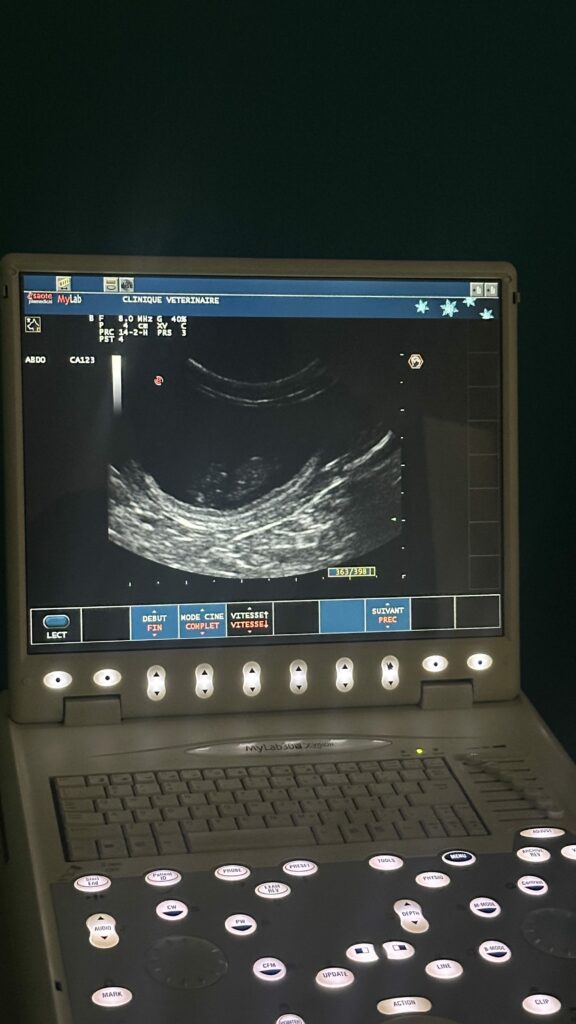

Inutile de se faire belle le jour J ! Effectivement, à la naissance, les chatons sont de petits explorateurs encore fragiles qui viennent au monde sourds et aveugles. Ce n’est qu’après une dizaine de jours qu’ils ouvrent enfin les yeux pour découvrir la douceur du monde. Mais heureusement, la nature est bien faite, et nous serons là pour les accompagner à chaque pas.